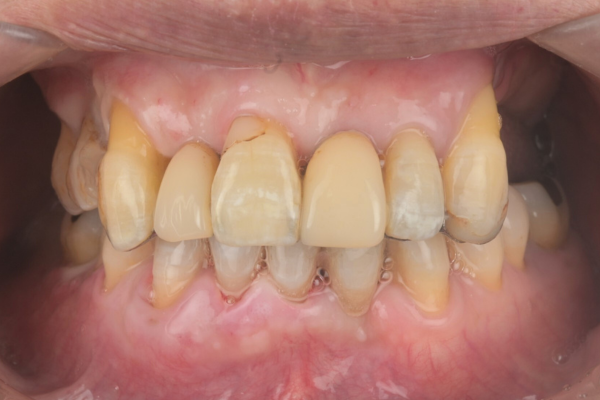

【術前】

2. ご来院時の状態と診断

精密検査(パノラマX線写真、口腔内写真、歯周病精密検査)を行った結果、以下の状態が確認されました。

●歯周ポケットの深化

最大で10mmに達する非常に深いポケットが複数箇所に認められました。

●慢性的な排膿

歯肉に強い炎症があり、圧迫すると膿が出る状態でした。

●歯の動揺

特に下顎の前歯はグラつきが激しく、ワイヤーで隣の歯と連結固定しなければ維持できない状態でした。

●セルフケアの状態

驚くべきことに、TBI(ブラッシング指導)の必要がないほど、患者さんのセルフケアは完璧でした。

診断の結果、原因はケアの不足ではなく、「従来の治療では除去しきれなかった深層の歯周病菌」と、元々の「歯周病になりやすい体質(遺伝的要因や免疫応答の特性)」が複雑に絡み合っているものと考えられました。